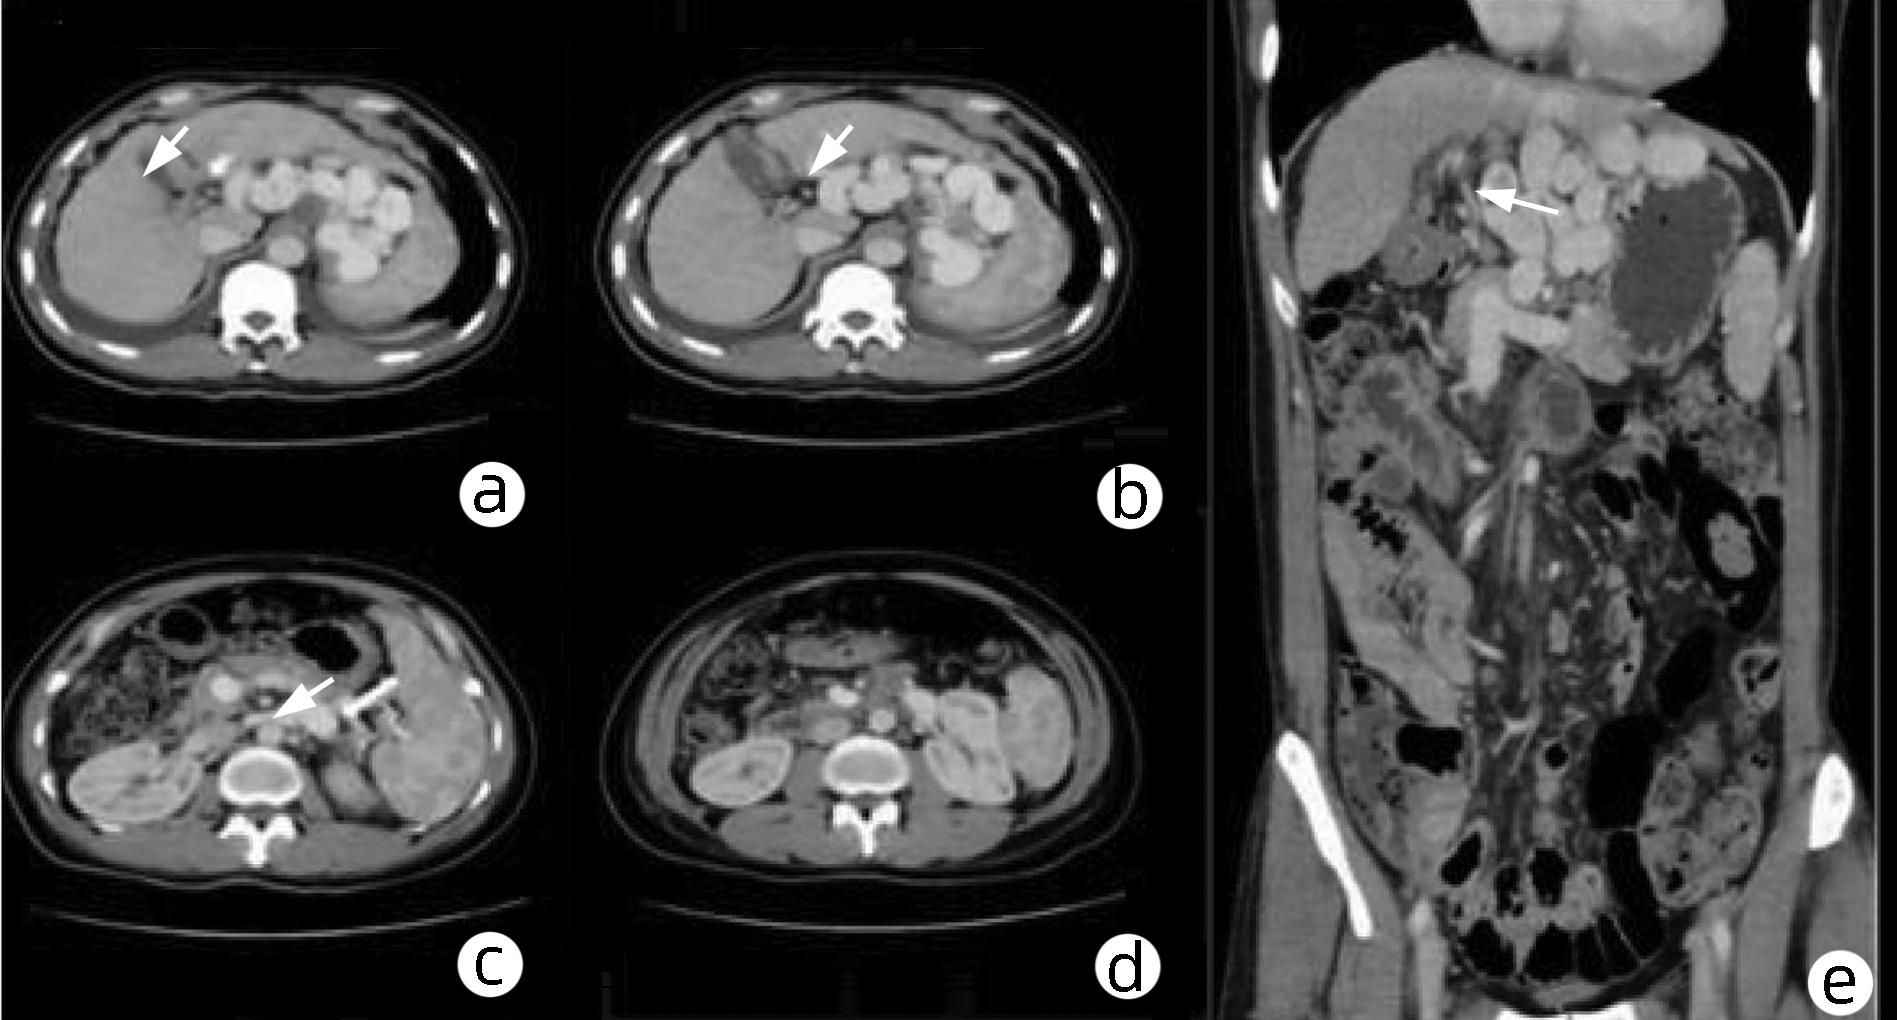

Massive hepatic hemangioma with diffuse arterioportal fistula: A case report

Bangjian ZHOU, Jun YANG, Yu YIN, Xiaoli ZHU, Caifang NI, Wansheng WANG

2023, 39(3): 640-643. DOI: 10.3969/j.issn.1001-5256.2023.03.025

Abstract(977) HTML (223) PDF (3500KB)(99)

Abstract: